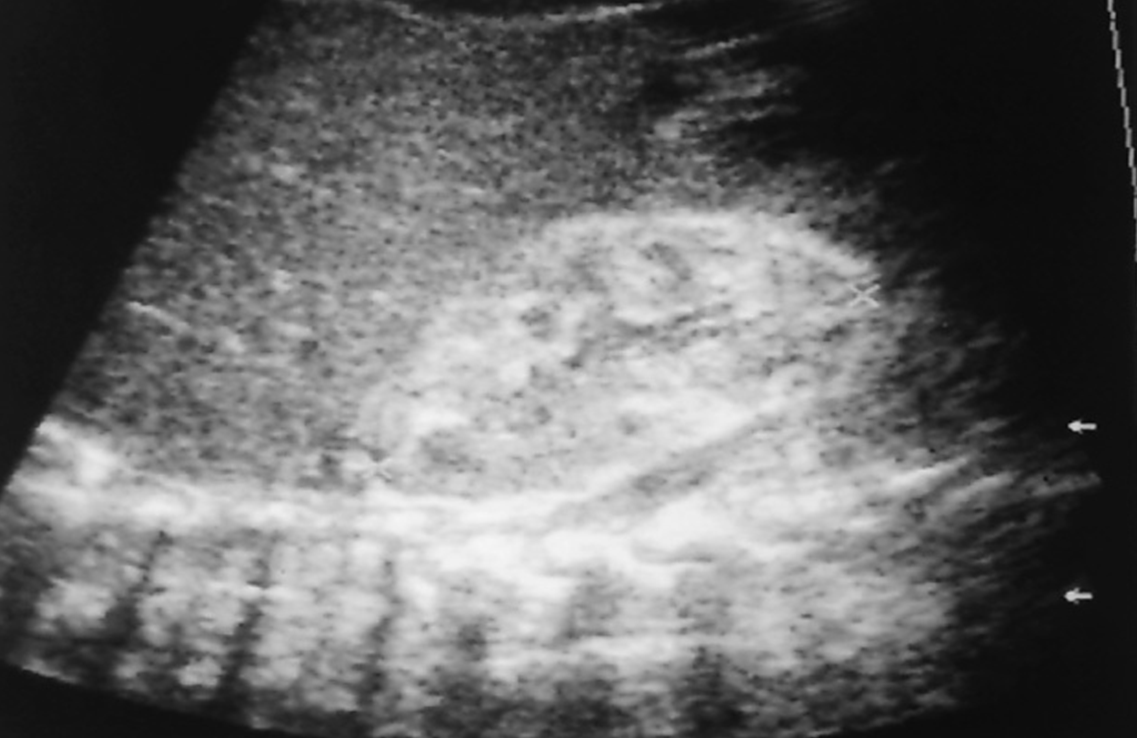

What are these images showing?

Angiomyolipoma